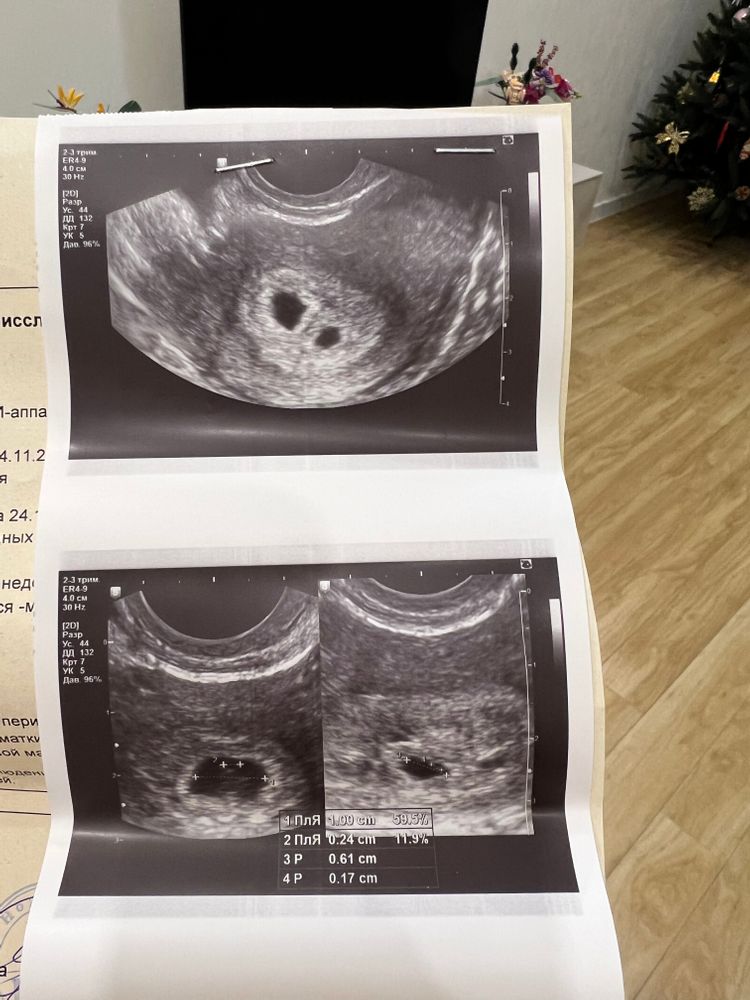

Гамлет вошел в чат и раздвоился 🙈моя интуиция меня не подводит … никогда ..

Мария , ну если верить узи, у вас диди(каждый в своём домике). Раз была овуляция значит второй еб. Баловались до или после овуляции?) Мне двоих посадили, двое и остались, у меня диди.

Пользователь бебиблога, да там до овуляции далековато было 🙈да и три года никак не получалось … никак 🫣посмотрим дальше - если разный пол, то однозначно еб 😂 Хотя тут писали что один раз раздваивался - на ди ) но Хорион то один вроде …

Мария , вообще одно плодное яйцо меньше, это доказывает, что они разные. Но раз один хорион прям и не знаю, мб ещё появится второй хорион?) Если появится, точно второй еб. Чудеса перед нг да и только) Пишите, не пропадайте))